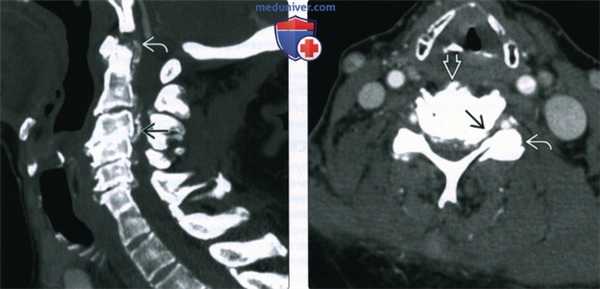

(Слева) КТ, сагиттальная проекция, с контрастным усилением: признаки многоуровневого спондилеза шейного отдела позвоночника с выраженным стенозом позвоночного канала. Визуализируется многоуровневое поражение дисков со склерозом замыкательных пластинок. Часто имеет место гипертрофия кости вокруг С1-С2. Обызвествление задней продольной связки способствует развитию стеноза.

(Справа) КТ, аксиальная проекция, с контрастным усилением: выраженный двухсторонний фораменальный стеноз с гипертрофией унковертебральных суставов у этого же пациента. Также визуализируются признаки деформирующего спондилеза и гипертрофия дугоотростчатых суставов.